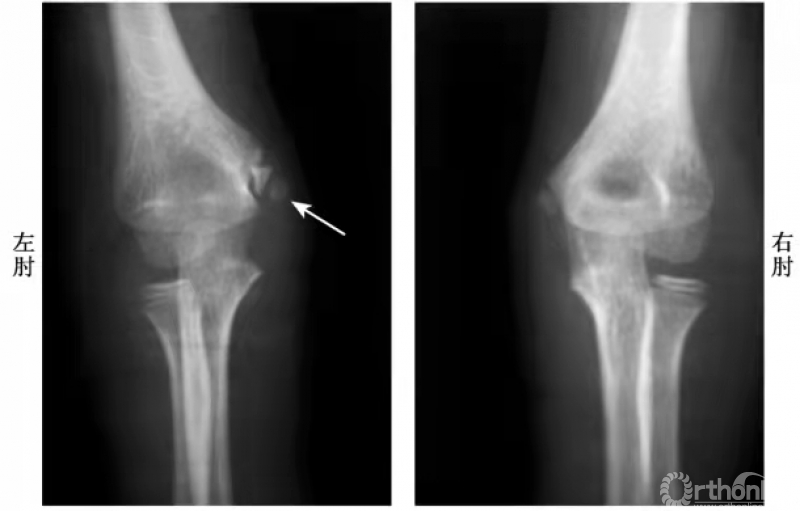

肱骨内上髁骨折可根据损伤严重程度分为四型。Ⅰ型损伤:内上髁骨骺分离稍有变位。Ⅱ型损伤:撕脱的内上髁骨骺向下、向前旋转移位,可达关节水平。Ⅲ型损伤:撕脱的内上髁骨骺嵌夹在内侧关节间隙,实际上肘关节处于半脱位状态。Ⅳ型损伤:肘关节向后或向后外侧脱位,撕脱的内上髁骨骺嵌夹在关节内。

Ⅰ度损伤:

例:内上髁骨骺并带一皮质骨片略下移位(图3)

图3

Ⅱ度损伤:

例1:内上髁骨骺分离并带一模糊的骨皮质,并向外侧旋转,而达关节水平(图4)。

图4